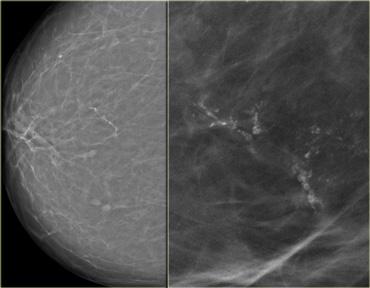

Bên trái là hình ảnh của một bệnh nhân với một vài vôi hóa thô không đồng nhất.

Chúng được phân loại là BIRADS 3 (có khả năng lành tính với xác suất ác tính dưới 3%).

Tại lần theo dõi sáu tháng, số lượng vôi hóa đã tăng lên và kết quả sinh thiết phát hiện DCIS.